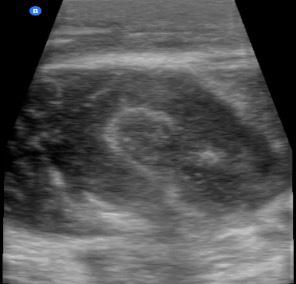

Dr. Artiga’s academic interests include ultrasound, education, and advocacy. Within SAEM RAMS, he has led initiatives such as the Ask-A-Chair educational podcast series, advocacy efforts related to unionization, social media campaigns to promote resident engagement, and the development of board review resources for emergency medicine certification. He has recently taught ultrasound to emergency medicine programs in Latin America.

It was an extremely humbling and eye-opening experience. I went to teach in my father’s country, El Salvador, where I had never visited before. I never truly understood the conditions he lived in beyond his words. All the issues that exist in the U.S. are magnified when you go to countries that don’t have similar resources. Medical decision making is limited by access to resources. It’s not about a lack of capability. I worked with incredibly brilliant doctors who just don’t have access to the same technology or infrastructure we have here. That’s why I believe in supporting ultrasound specifically in these settings. In capable hands, point-ofcare ultrasound can give a clinician life-saving information. Providing this tool and empowering physicians to use it can have a huge impact on individual patients and healthcare systems across the world.

For me, it’s been about chasing my passion and asking, “Who’s on this ride with me?” I’ve always been drawn to ultrasound. Through SAEM’s and the Academy for Emergency Ultrasound’s (AEUS’s) ultrasound didactics and activities, I’ve noticed similar faces showing up. These spaces allow for ideas to connect and develop in ways that don’t happen when you're working alone. You can’t have synergy in isolation. You need people who challenge and inspire you to promote growth. It’s individuals working together, learning from one another, and pushing ideas forward that produce progress.